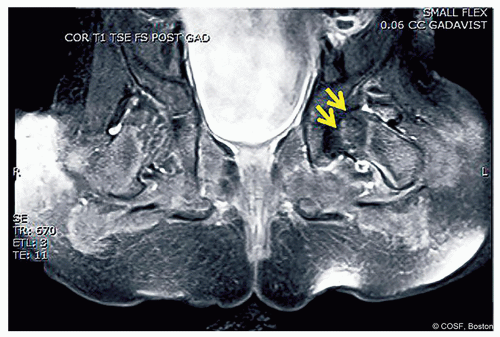

Figure 20-1 ▪ Arthrogram of subluxated left hip. (Courtesy of Children’s Orthopaedic Surgery Foundation.)

In dislocated hip, try to insert into the vacant acetabulum in the inferior side (Figure 20.1)

In subluxated/dysplastic hips, flex hip and aim for the proximal portion of the inferior femoral neck

Once in cast, if position of the hip is in question, after sterile swab of the exposed groin, you can repeat the arthrogram in cast (Figure 20.2)